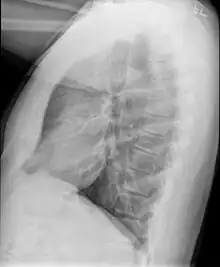

Medical imaging

Early in the disease chest radiography is typically normal but may show hyperinflation.[6] As the disease progresses a reticular pattern with thickening of airway walls may be present.[4][6] HRCT can also show air trapping when the person being scanned breathes out completely; it can also show thickening in the airway and haziness in the lungs.[11] A common finding on HRCT is patchy areas of decreased lung density, signifying reduced vascular caliber and air trapping. This pattern is often described as a "mosaic pattern", and may indicate bronchiolitis obliterans.[6]